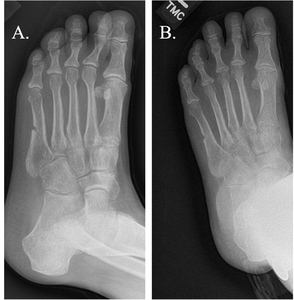

The average time from nonunion diagnosis until successful healing was 154.7 days following PEMF treatment. The majority of subjects (n=35/56, 62.5%) were categorized as healed with by four months post-PEMF initiation and 75.0% of subjects (n=42/56) were healed by six months. (Table 3; Figure 1; Figure 2) Representative radiographic images are presented in Figure 3. The number of risk factors (up to 5 total per subject) were significantly associated with longer heal times (p < 0.02). Of the individual risk factors studied, only nicotine use was associated with longer healing times (p < 0.03). (Table 4)